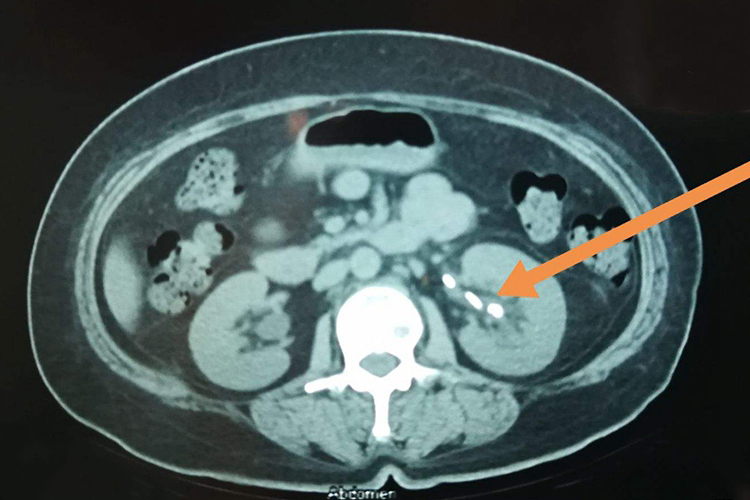

尿结石CT片子主要可见尿路部位出现白色高密度影,结石上方还可出现输尿管扩张,肾盂、肾盏积水及梗阻性肾实质像。

CT平扫可见肾、输尿管、膀胱等单一或多个部位出现大小、数目、形状、位置较为准确的结石白色高密度影,增强CT能够显示肾脏积水的程度和肾实质的厚度,因此还可见结石上方出现输尿管扩张,肾盂、肾盏积水及梗阻性肾实质像。